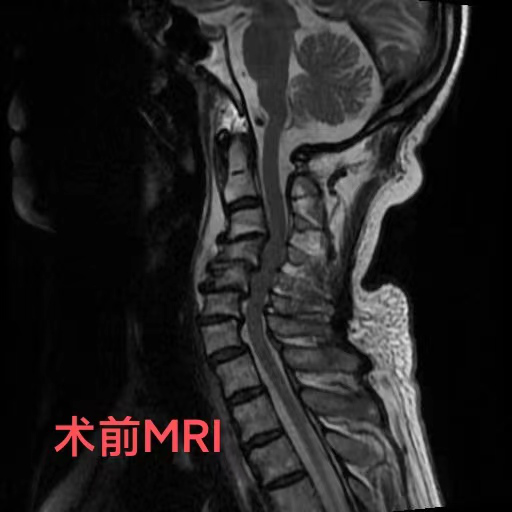

近日,74岁的陈爷爷,由于出现颈部疼痛、手脚麻木、行走困难等症状被家人送到重庆医科大学附属璧山医院(重庆市璧山区人民医院)康复医学科就诊。科室罗秋红主治医师为其进行了颈椎核磁共振检查,结果提示,患者颈椎变形已导致脊髓神经受压,随时有高位截瘫的风险。陈爷爷患有颈椎病多年,因担心手术带来的风险,长期依靠理疗来缓解病痛,这次也是因为症状日趋严重,无奈之下才前来就医。

罗医生第一时间联系了神经外科脊柱脊髓组的邓雷主治医师。针对陈爷爷及其家属的担忧,邓雷主治医师进行了耐心细致的沟通,最终陈爷爷决定配合医护进行手术治疗。患者高龄且有基础疾病,手术方案需要慎之又慎。神经外科副主任(主持工作)徐忠烨主任医师组织全科医生根据患者具体病情,制定了最终方案:前路3节段颈椎间盘切除+颈椎后凸畸形矫正。

陈爷爷长期的颈椎变形产生了大量骨质增生,给术中的邓雷、蒋登志医生出了难题。在神经显微镜下,他们的眼睛如鹰,指尖之中飞舞最温柔的神经刀锋,雕塑着最坚硬的颈椎骜骨。最终,手术耗时两个半小时,成功矫正,没有神经损伤!患者术后3天康复出院。